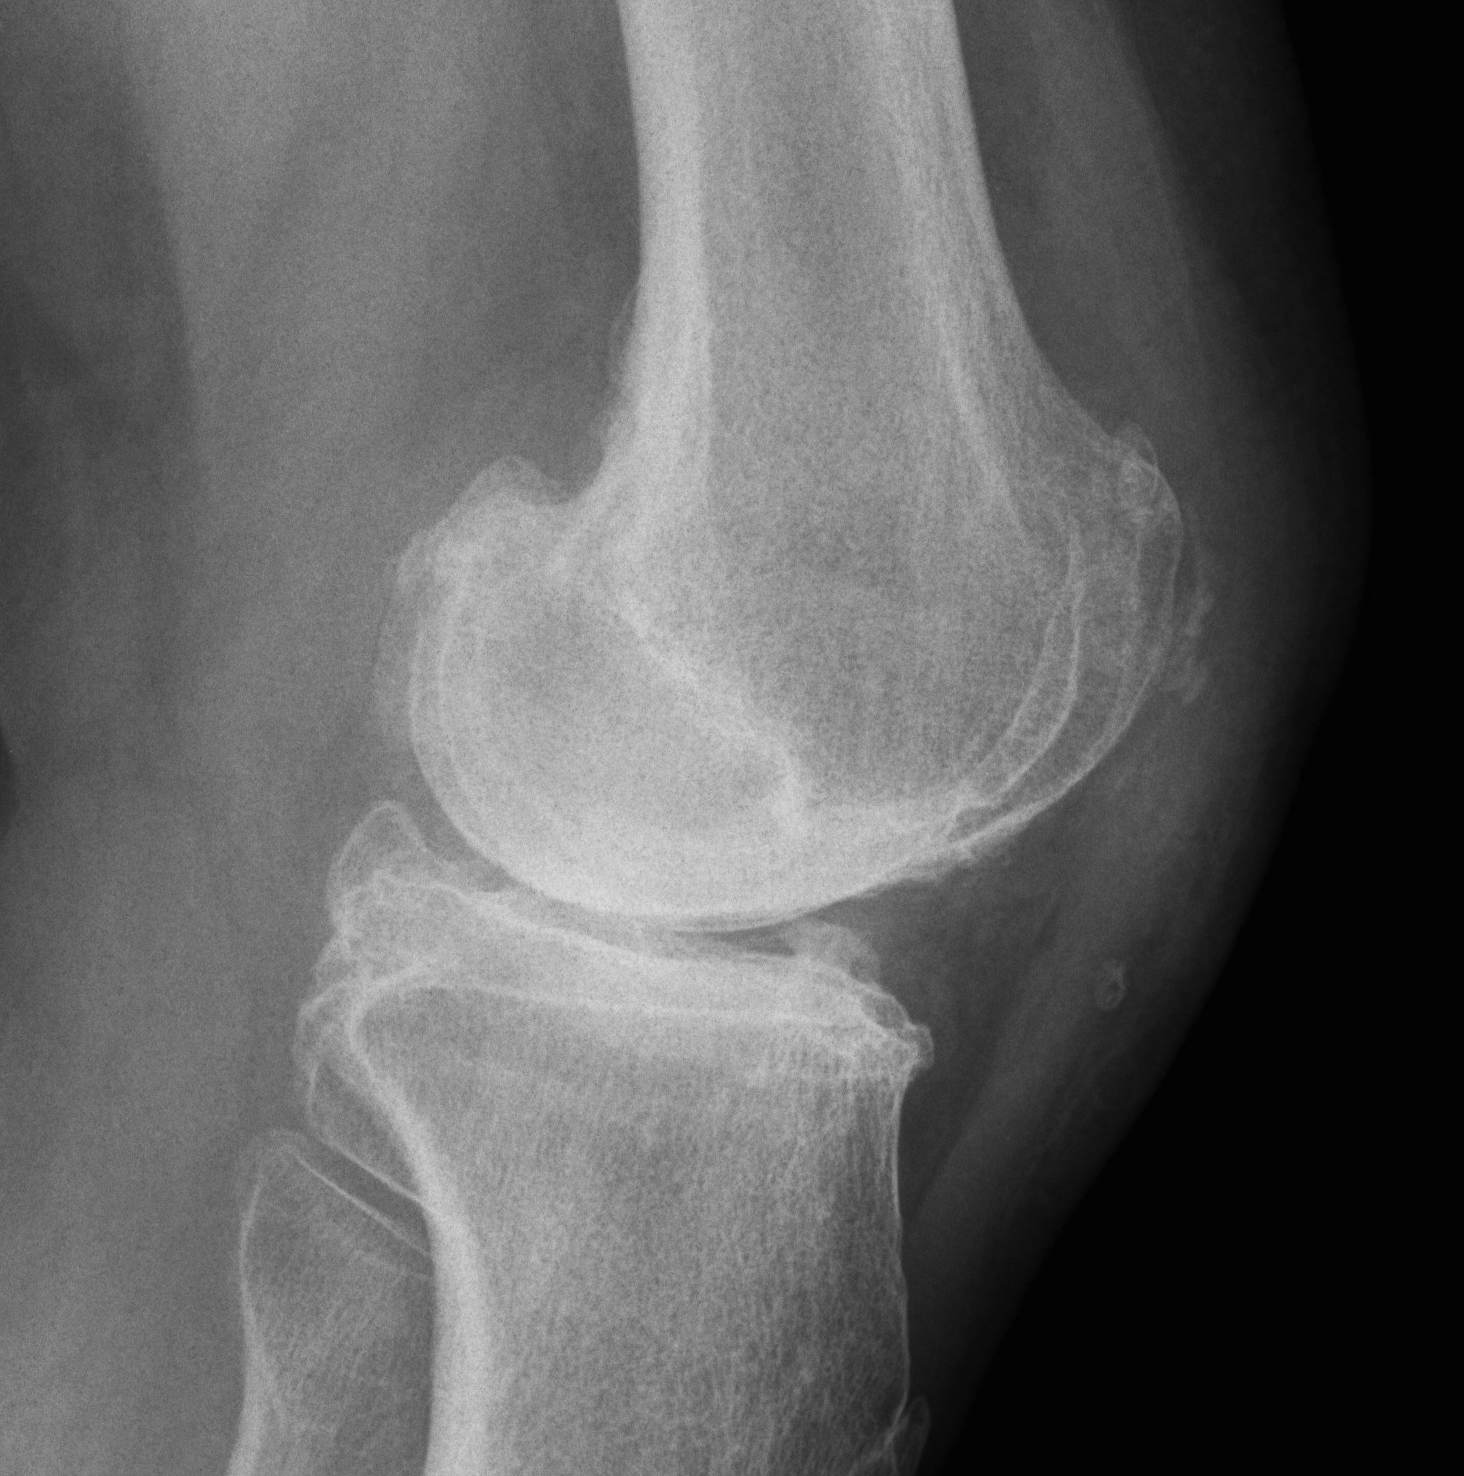

MRI

Moderate lateral facet PJF OA with tilt

Severe lateral PFJ OA in the setting of maltracking / subluxation / tilt